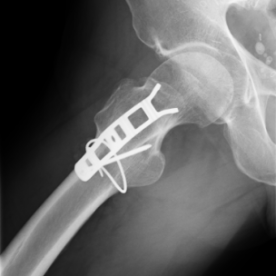

Röntgenbilder